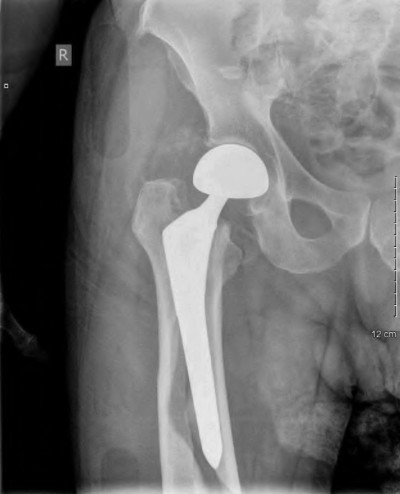

A 72-year-old female falls and sustains a periprosthetic femur fracture around her cementless total hip arthroplasty. Radiographs reveal a fracture extending just distal to the tip of the stem. The stem is radiographically loose, but there is excellent proximal and distal bone stock. According to the Vancouver classification, what is the fracture type and the recommended surgical treatment?

A 75-year-old female sustains a fall 5 years after a cementless THA. Radiographs show a periprosthetic femur fracture occurring around the stem tip. Intraoperative assessment reveals the stem remains firmly fixed in the metaphysis, and the proximal bone stock is adequate. According to the Vancouver classification, what is the fracture type and the standard recommended treatment?